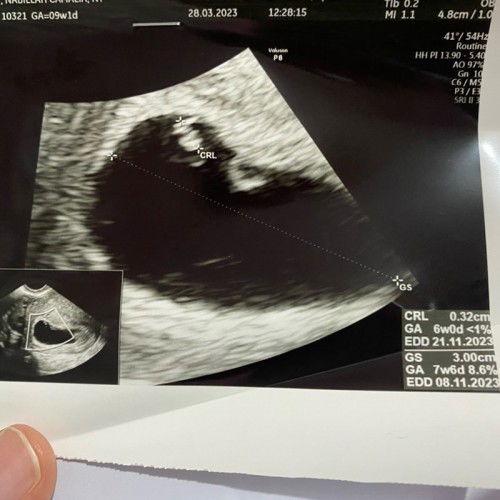

Janin tidak berkembang?

Bunda ada yg seperti ini? Klo menurut hitungan hpht sy usia 9w1d, usia kantung/gs 7w6d tapiiii usia janin 6w. Kata dokter tdk berkembang krn ukuran janin tdk sesuai usia kehamilan dan tdk ada djj Tdk ada flek/pendarahan dan tdk ada kram perut